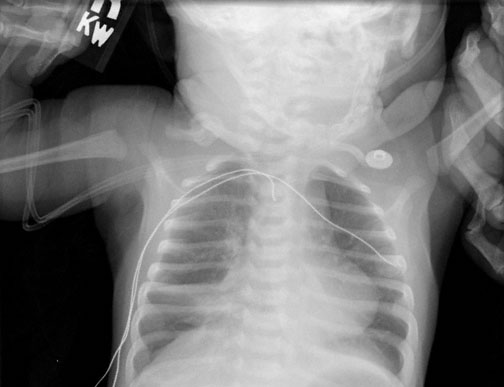

A 2-month-old boy is brought to the emergency department by his parents 30 minutes after he stopped breathing and turned blue while the parents were laying him down for a nap. They say he resumed breathing after 25 seconds when they rubbed his chest. He has a 1-day history of cough, nasal congestion, and decreased feeding and activity. He has not had fever. He has no history of serious illness and receives no medications. Vaccinations are up-to-date. Temperature is 37.9°C (100.3°F), pulse is 140/min, respirations are 65/min, and blood pressure is 100/70 mm Hg. Pulse oximetry on room air shows an oxygen saturation of 90%. Examination shows nasal congestion and rhinorrhea. Diffuse wheezes are heard bilaterally, and there are subcostal retractions. The remainder of the examination discloses no abnormalities. Chest x-ray is shown. Which of the following is most likely to confirm the etiology of this patient’s episode?